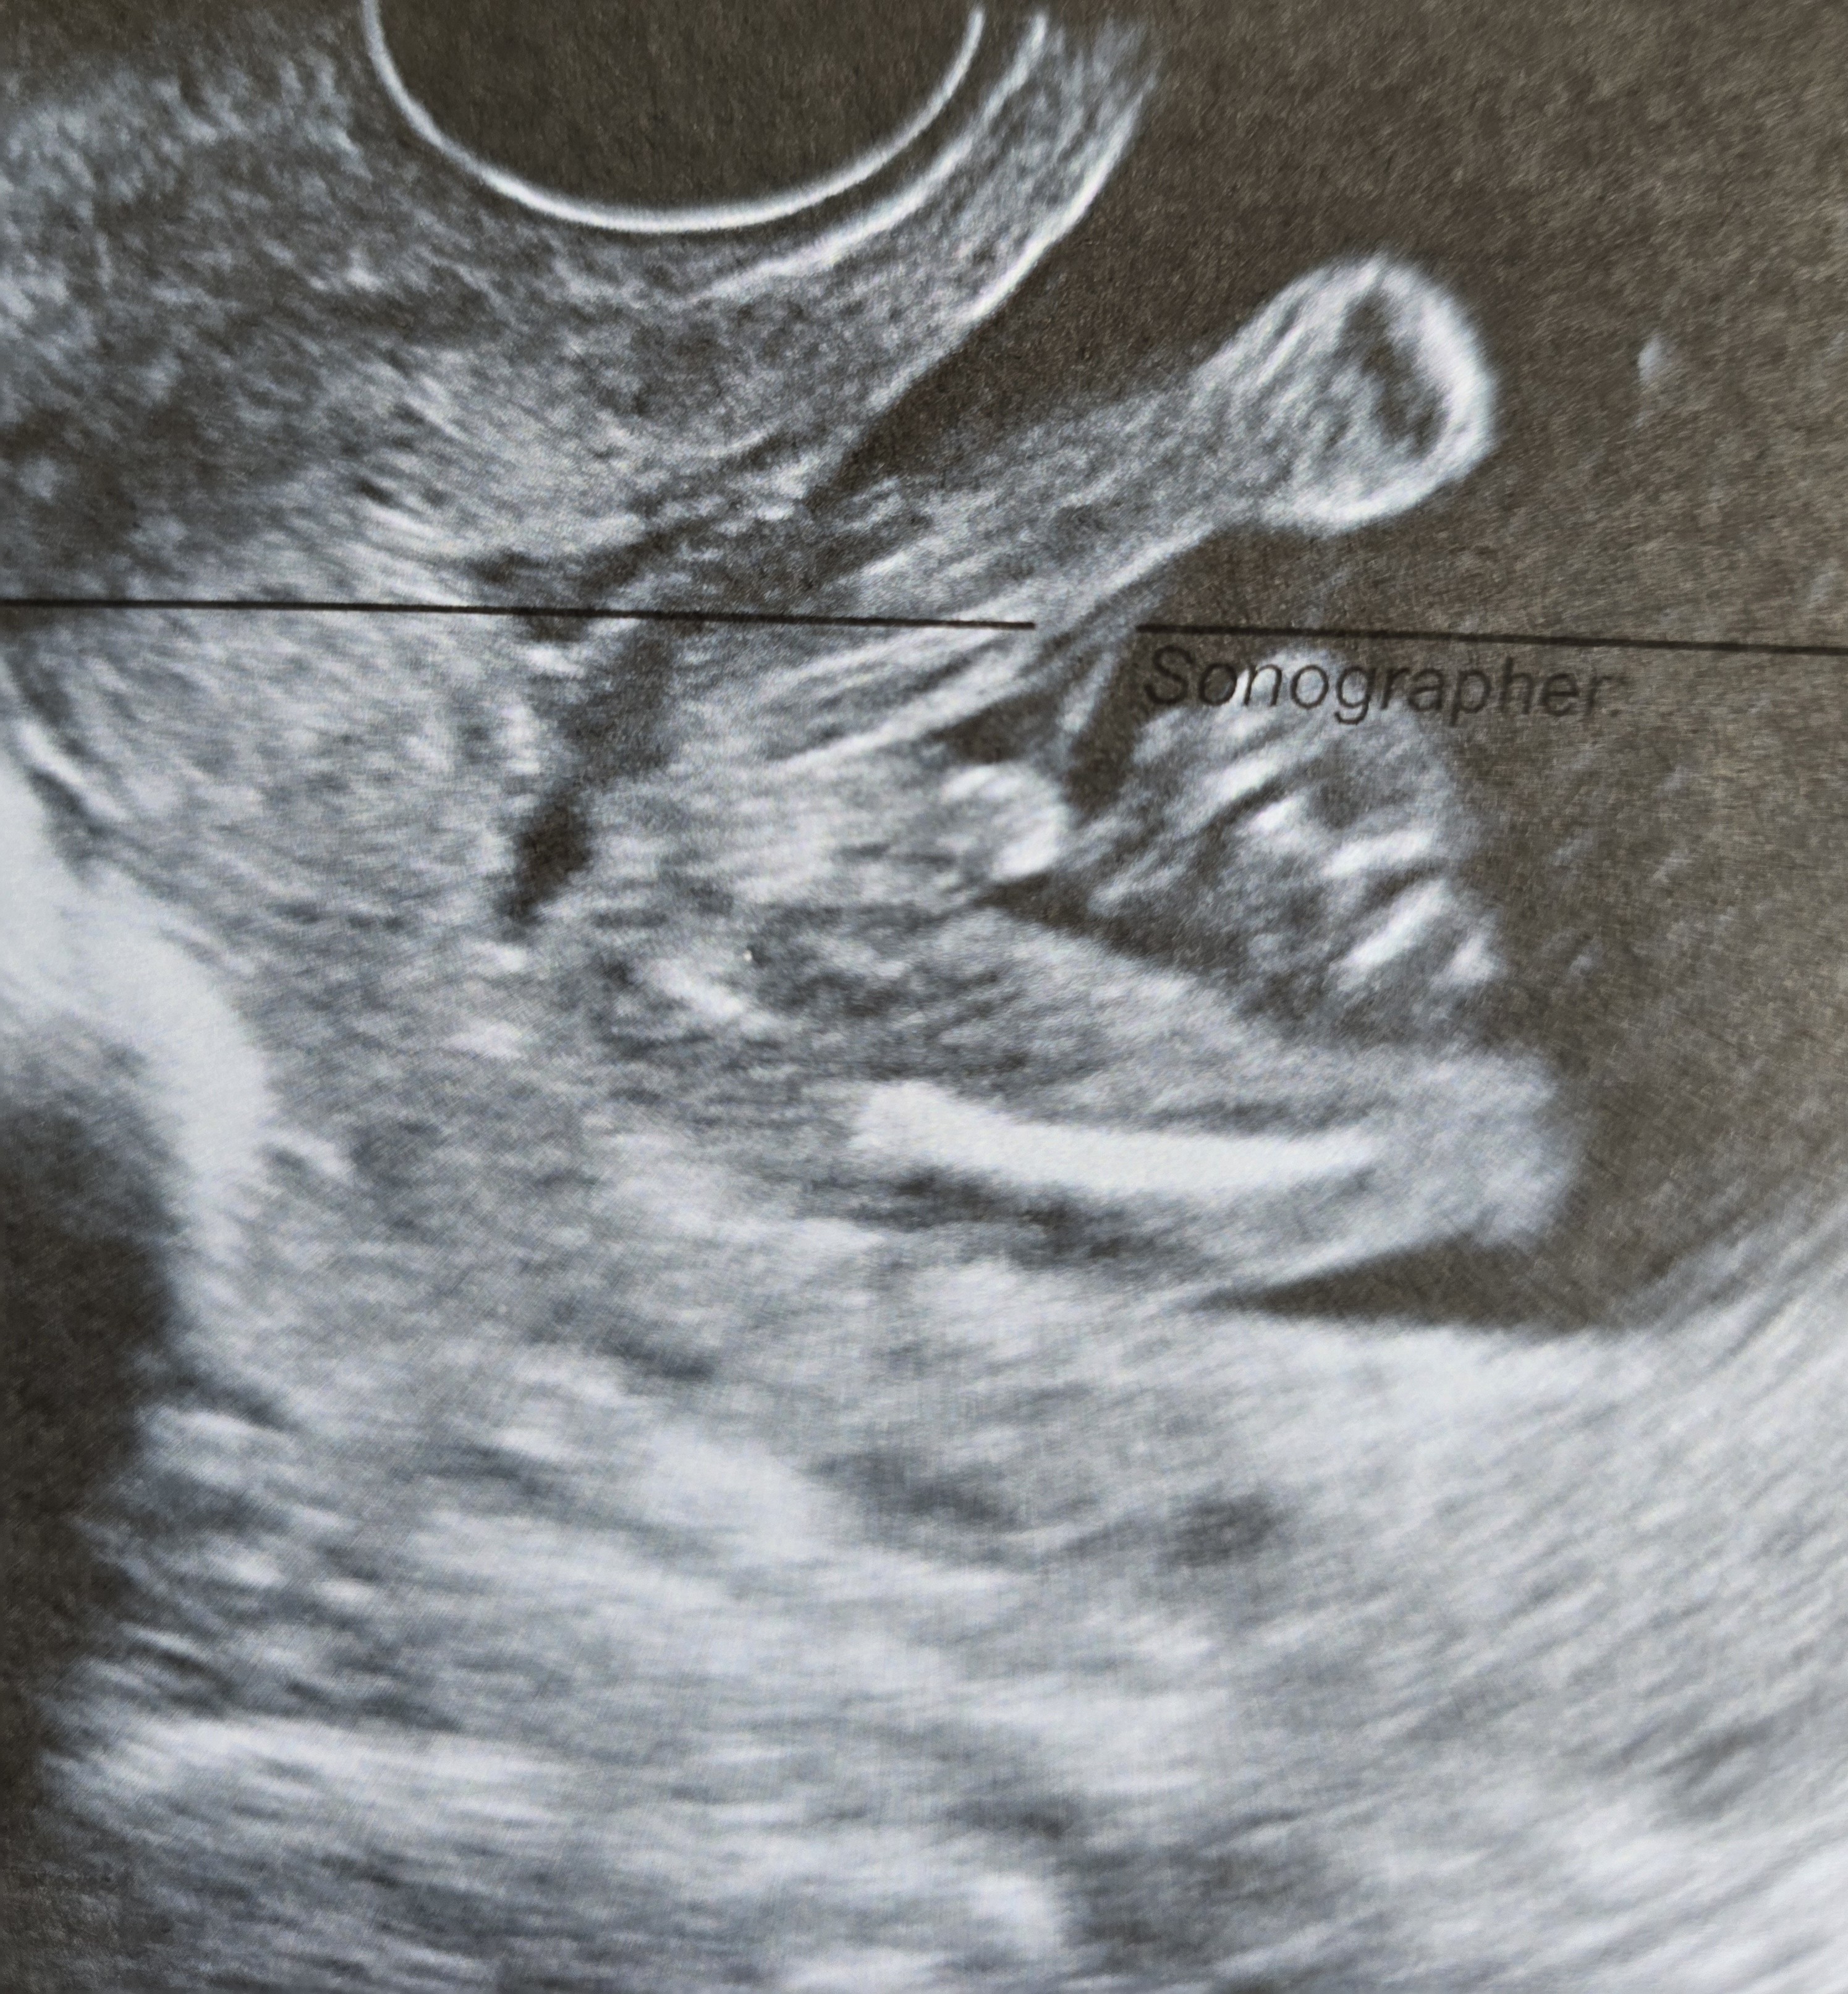

Z takiego zdjęcia nic Ci nie powiem. Ja się opieram na nub. Przykłady:

Zobacz załącznik 1657680

Zobacz załącznik 1657681